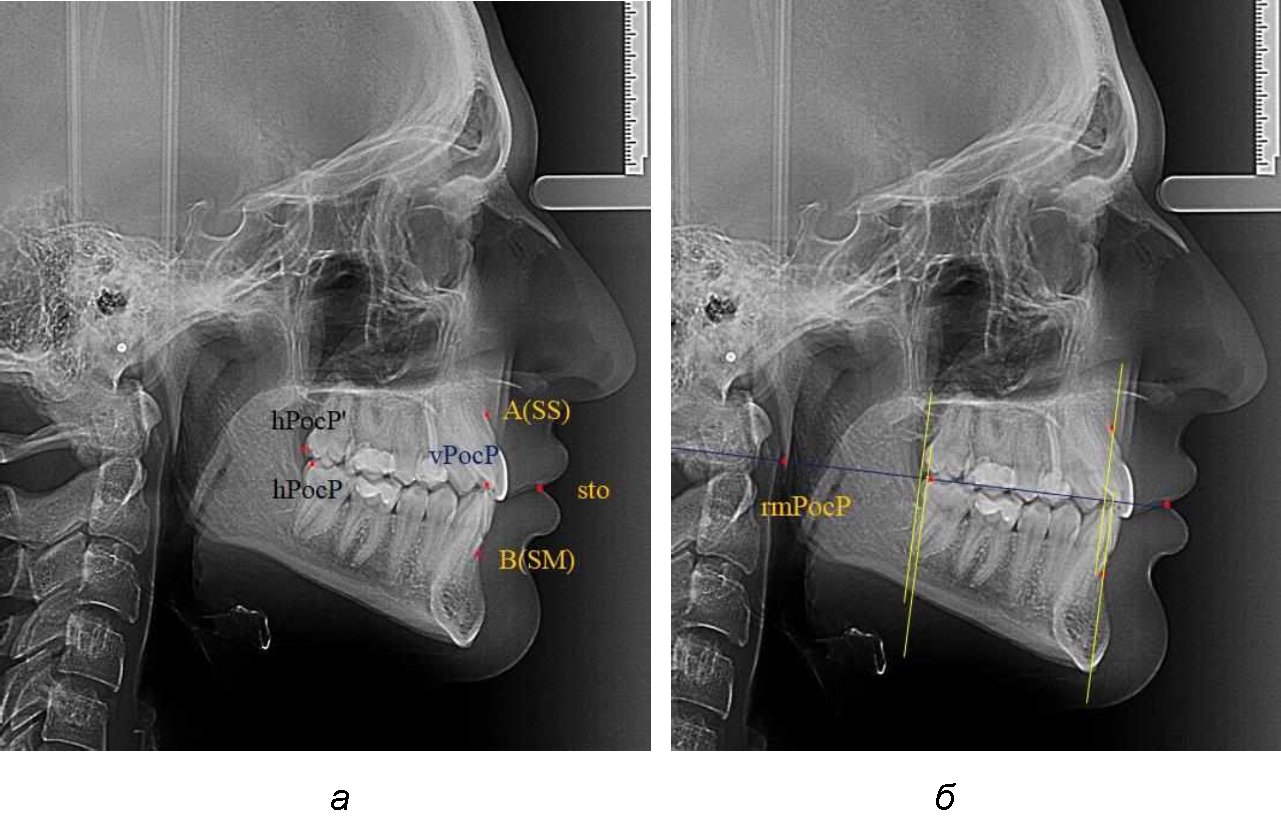

На рентгенограммах устанавливали точки Downs. На верхней челюсти субспинальная точка A(SS) располагалась в наиболее вогнутой точке альвеолярного отростка по переднему его краю. На нижней челюсти супраментальная точка B(SM) соответствовала месту наибольшей вогнутости переднего края альвеолярной части. Окклюзионную линию проводили через контактную точку резцов (vРOcP) и дистальную точку окклюзии второго нижнего моляра (hРOcP). Место пересечения окклюзионной линии с дистальным краем ветви нижней челюсти (ramus mandibule) обозначали как «rmРOcP». Перпендикулярно к окклюзионной плоскости проводили линии из точек «А(SS)» и «В(SМ)», что определяло их проекцию на окклюзионную линию. Аналогично отмечали положения дистальных окклюзионных точек верхней и нижней челюсти (рис. 1).

Рис. 1. Положение основных точек (а) и линейных ориентиров (б) для анализа положения и размеров челюстей

Альвеолярно-дентальный размер верхней челюсти и нижней челюсти оценивали по окклюзионной линии между вертикалями, ограничивающими исследуемые челюсти. Положение верхней челюсти оценивали по величине размера «rmOcP-А», а нижней челюсти по расстоянию «rmOcP-В». Линия смыкания губ обозначалась как точка «sto», вблизи которой проходила окклюзионная линия. Данный ориентир позволял провести окклюзионную плоскость при аномалиях положения резцов в вертикальном направлении, когда была сложность определения резцовой окклюзионной точки (vРOcP).

Аналогичное расстояние было отмечено и при расположении дистальных окклюзионных точек верхней и нижней челюсти (рис. 2).

Рис. 2. Положение апикальных точек и челюстей при нормопозиции (а), антепозиции (б) и ретропозиции (в) верхней челюсти